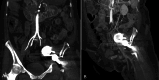

This case report evaluates current diagnostic and treatment approaches for intrapelvic acetabular migration, focusing on the rare but serious complication of acute limb ischemia following hip arthroplasty. A 67-year-old female with a history of total hip arthroplasty 10 years ago presented with acute limb ischemia after experiencing a traumatic event 72 hours prior, which had caused displacement of her hip prosthesis. Notably, she had a history of a traumatic event two years earlier for which she had been advised to undergo surgical correction, which she had refused. A multidisciplinary team assessed her preoperatively. She was diagnosed with SVS III irreversible acute limb ischemia due to compression of the external iliac artery from the prosthesis migration, prompting an emergency hip disarticulation. The patient successfully underwent hip disarticulation and mechanical thrombectomy of the external iliac artery using a Fogarty catheter. Postoperative recovery was notable, with significant pain relief, improved mental status, and restoration of the iliac pulse. Early diagnosis and management of acute arterial injury are crucial to preventing severe outcomes. This report highlights the importance of timely intervention to mitigate limb-threatening and life-threatening complications. It underscores the need for vigilant monitoring during hip replacements and the effectiveness of a multidisciplinary approach in complex cases. Continued research is essential to enhance diagnostic and therapeutic strategies for this rare yet critical complication and to improve overall patient outcomes.